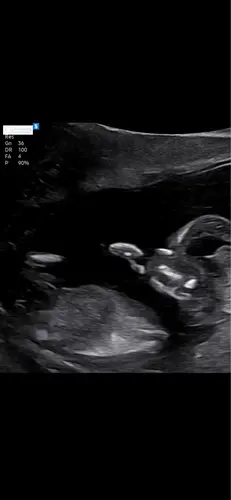

15+3 鉂わ笍

Net de 14 weken echo gehad. Wat denken jullie wat het is ?